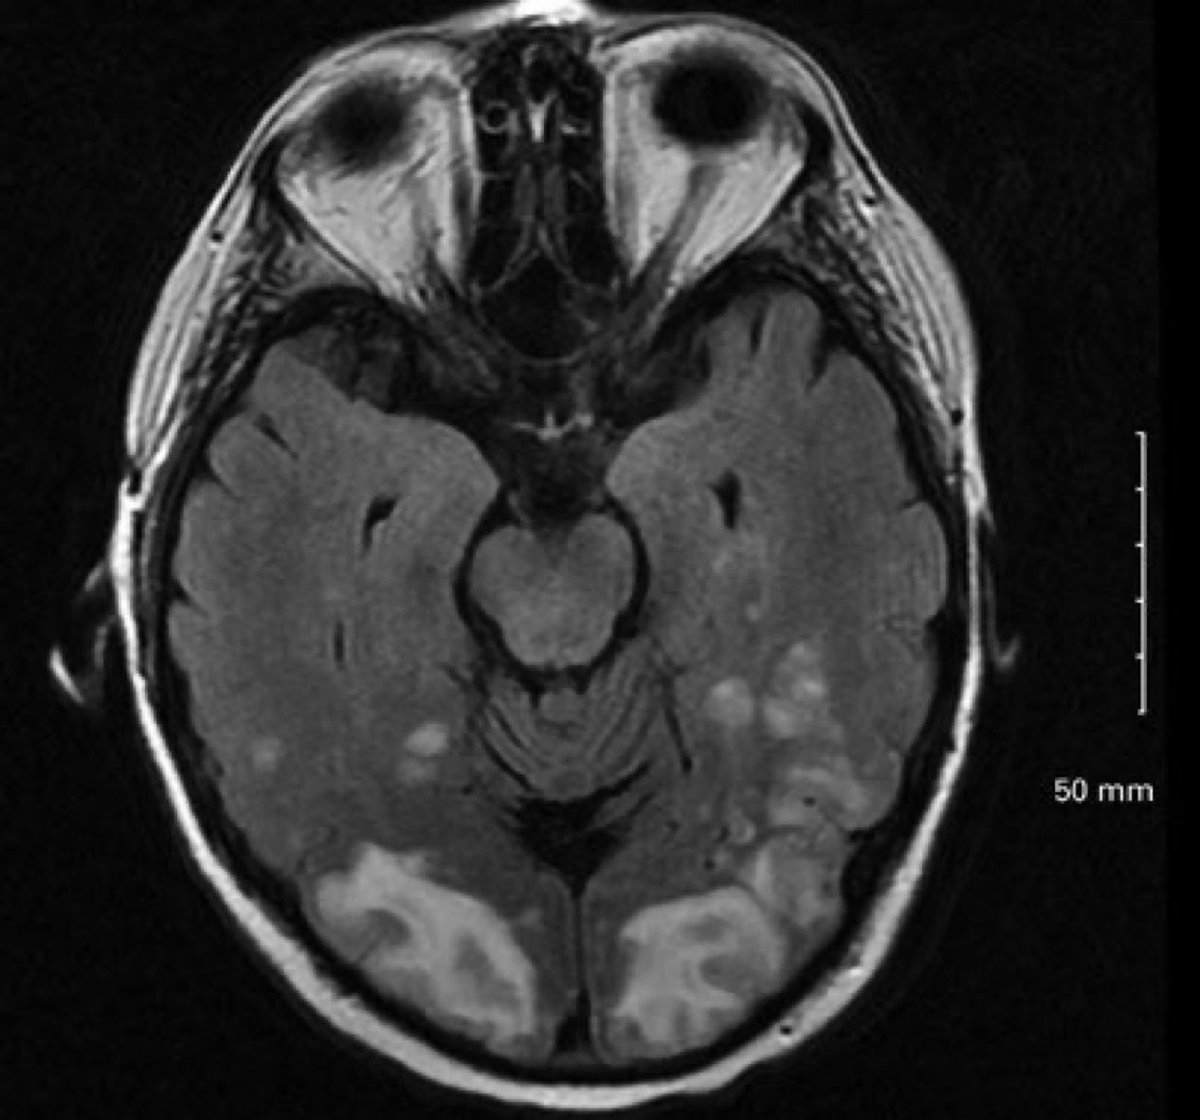

تشخيص مرعب جاء بضغط 200/120 ويقول ما عد صرت اشوف شيء ابدا !!! دكاترة العيون فحصوه اول، وقالوا مافي شيء من جانبنا وش التشخيص ؟! العلاج ؟ ⭐️⭐️⭐️⭐️⭐️⭐️⭐️⭐️⭐️⭐️⭐️⭐️⭐️⭐️⭐️